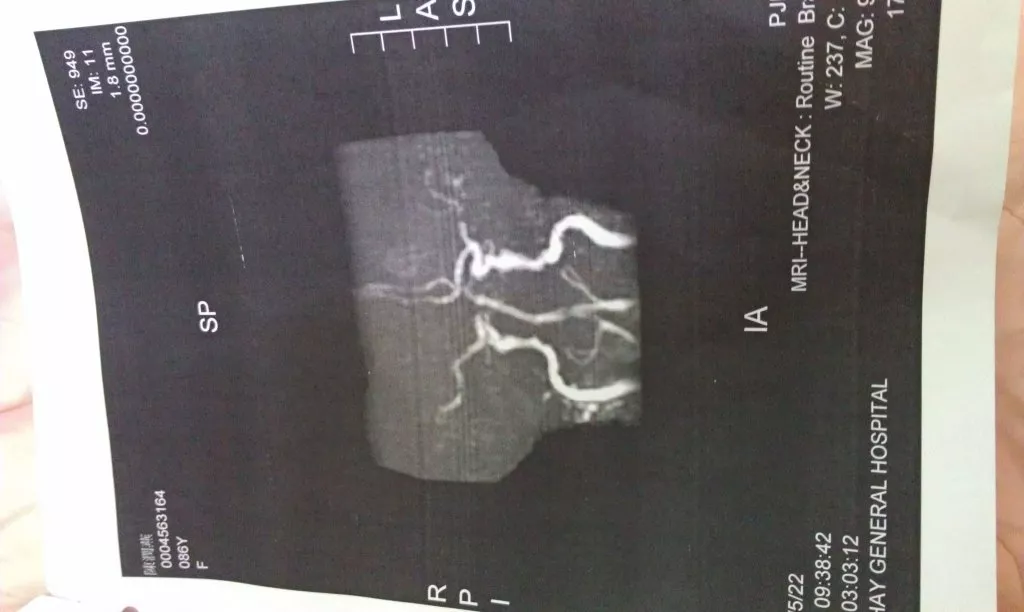

今天好奇寶寶老媽再次到地下一樓做MRI,週三下午作時因為老媽燥動,無法成影,醫事技術人員建議打鎮定劑,我還是要請問醫生有沒有風險?因為從老媽的狀況,就可以斷定是二度中風,MRI僅是確定中風的部位,這樣的風險是否值得?昨天乾弟妹提到他知道的朋友,因為打了鎮定劑不再醒來。好在老媽昨天晚上沒睡好,因禍得福,今天做MRI昏睡不醒,成功做了腦部影像。

5/21入院時剛照的MRI影像